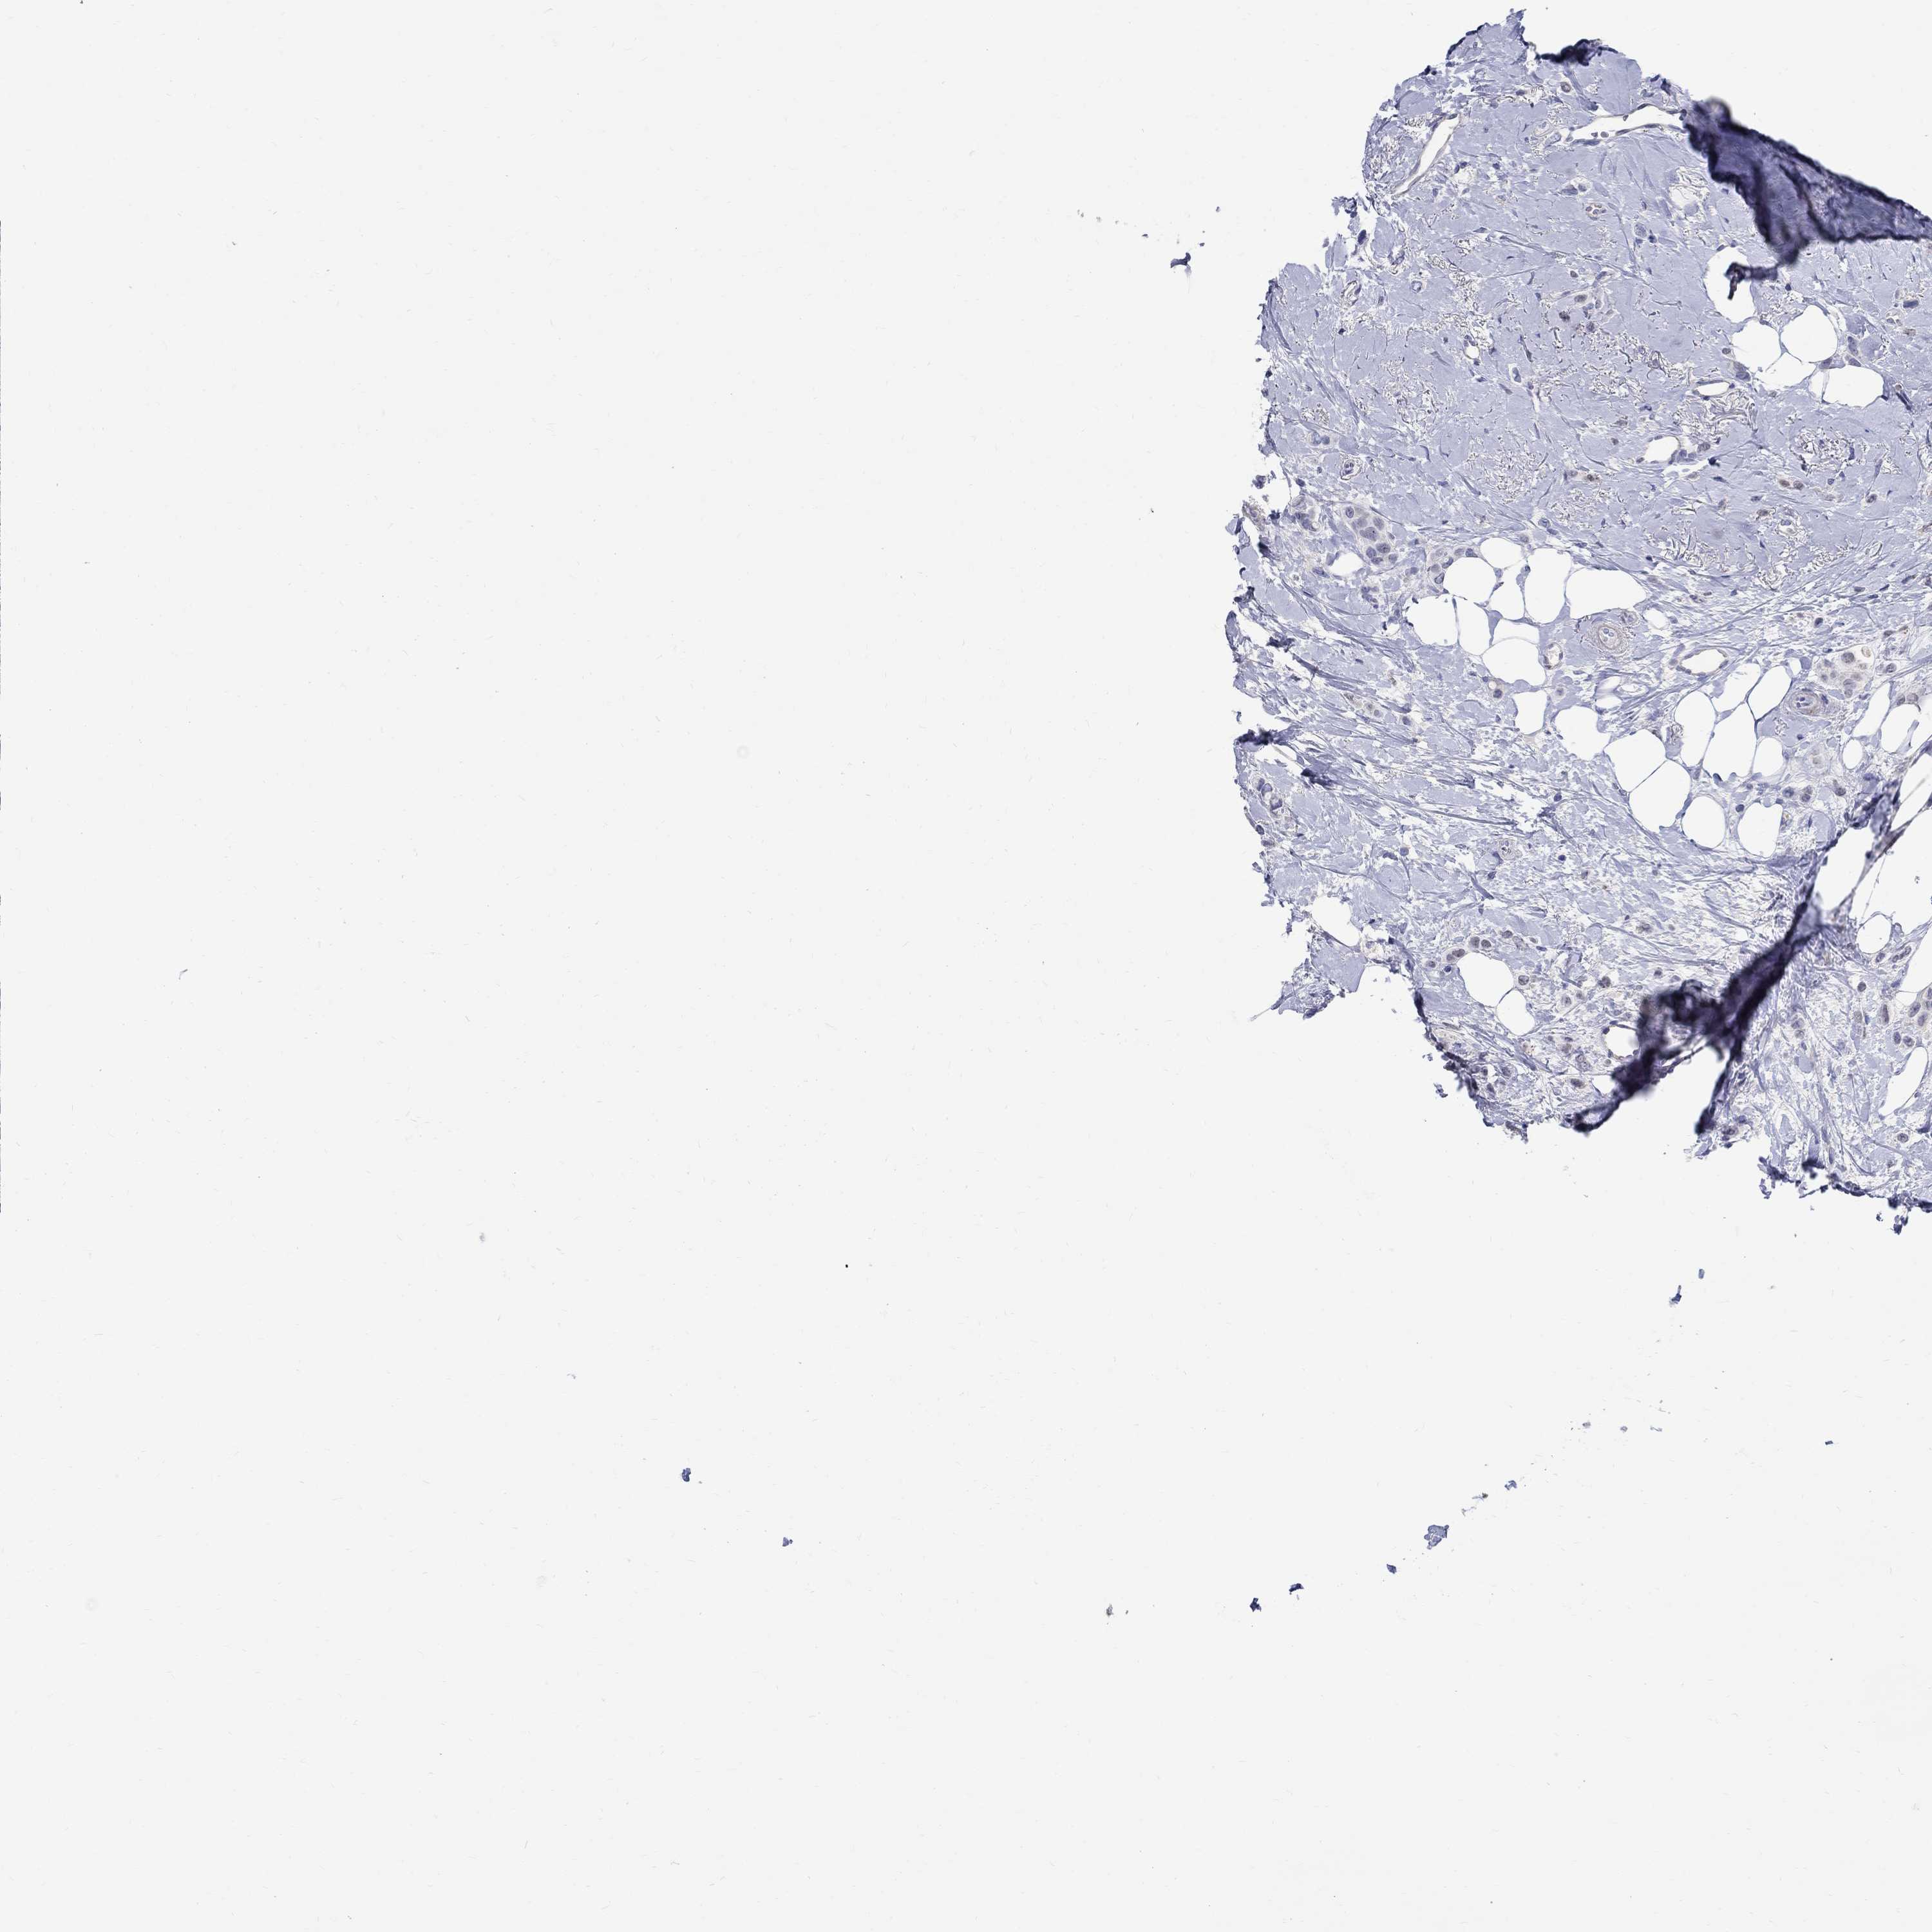

BRCA TCGA BRCA VALIDATION PROTEIN EXPRESSION

ANTIBODIES

AND

VALIDATION